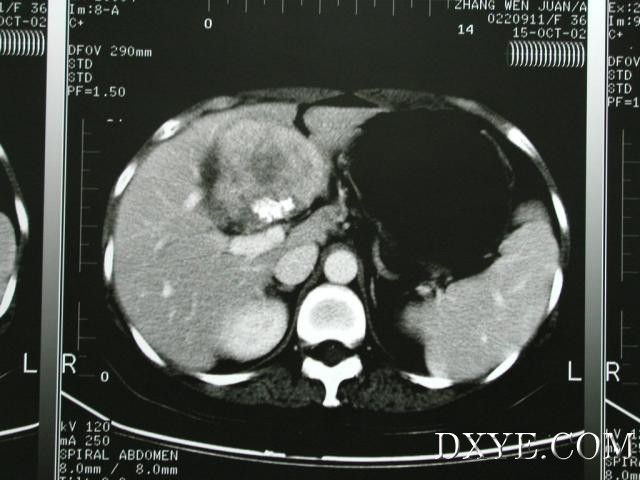

患者增强CT,见脾脏肿大,无腹水,肝左内叶占位性病变,位于门

静脉

主干正前方(门静脉左右支分叉处)。